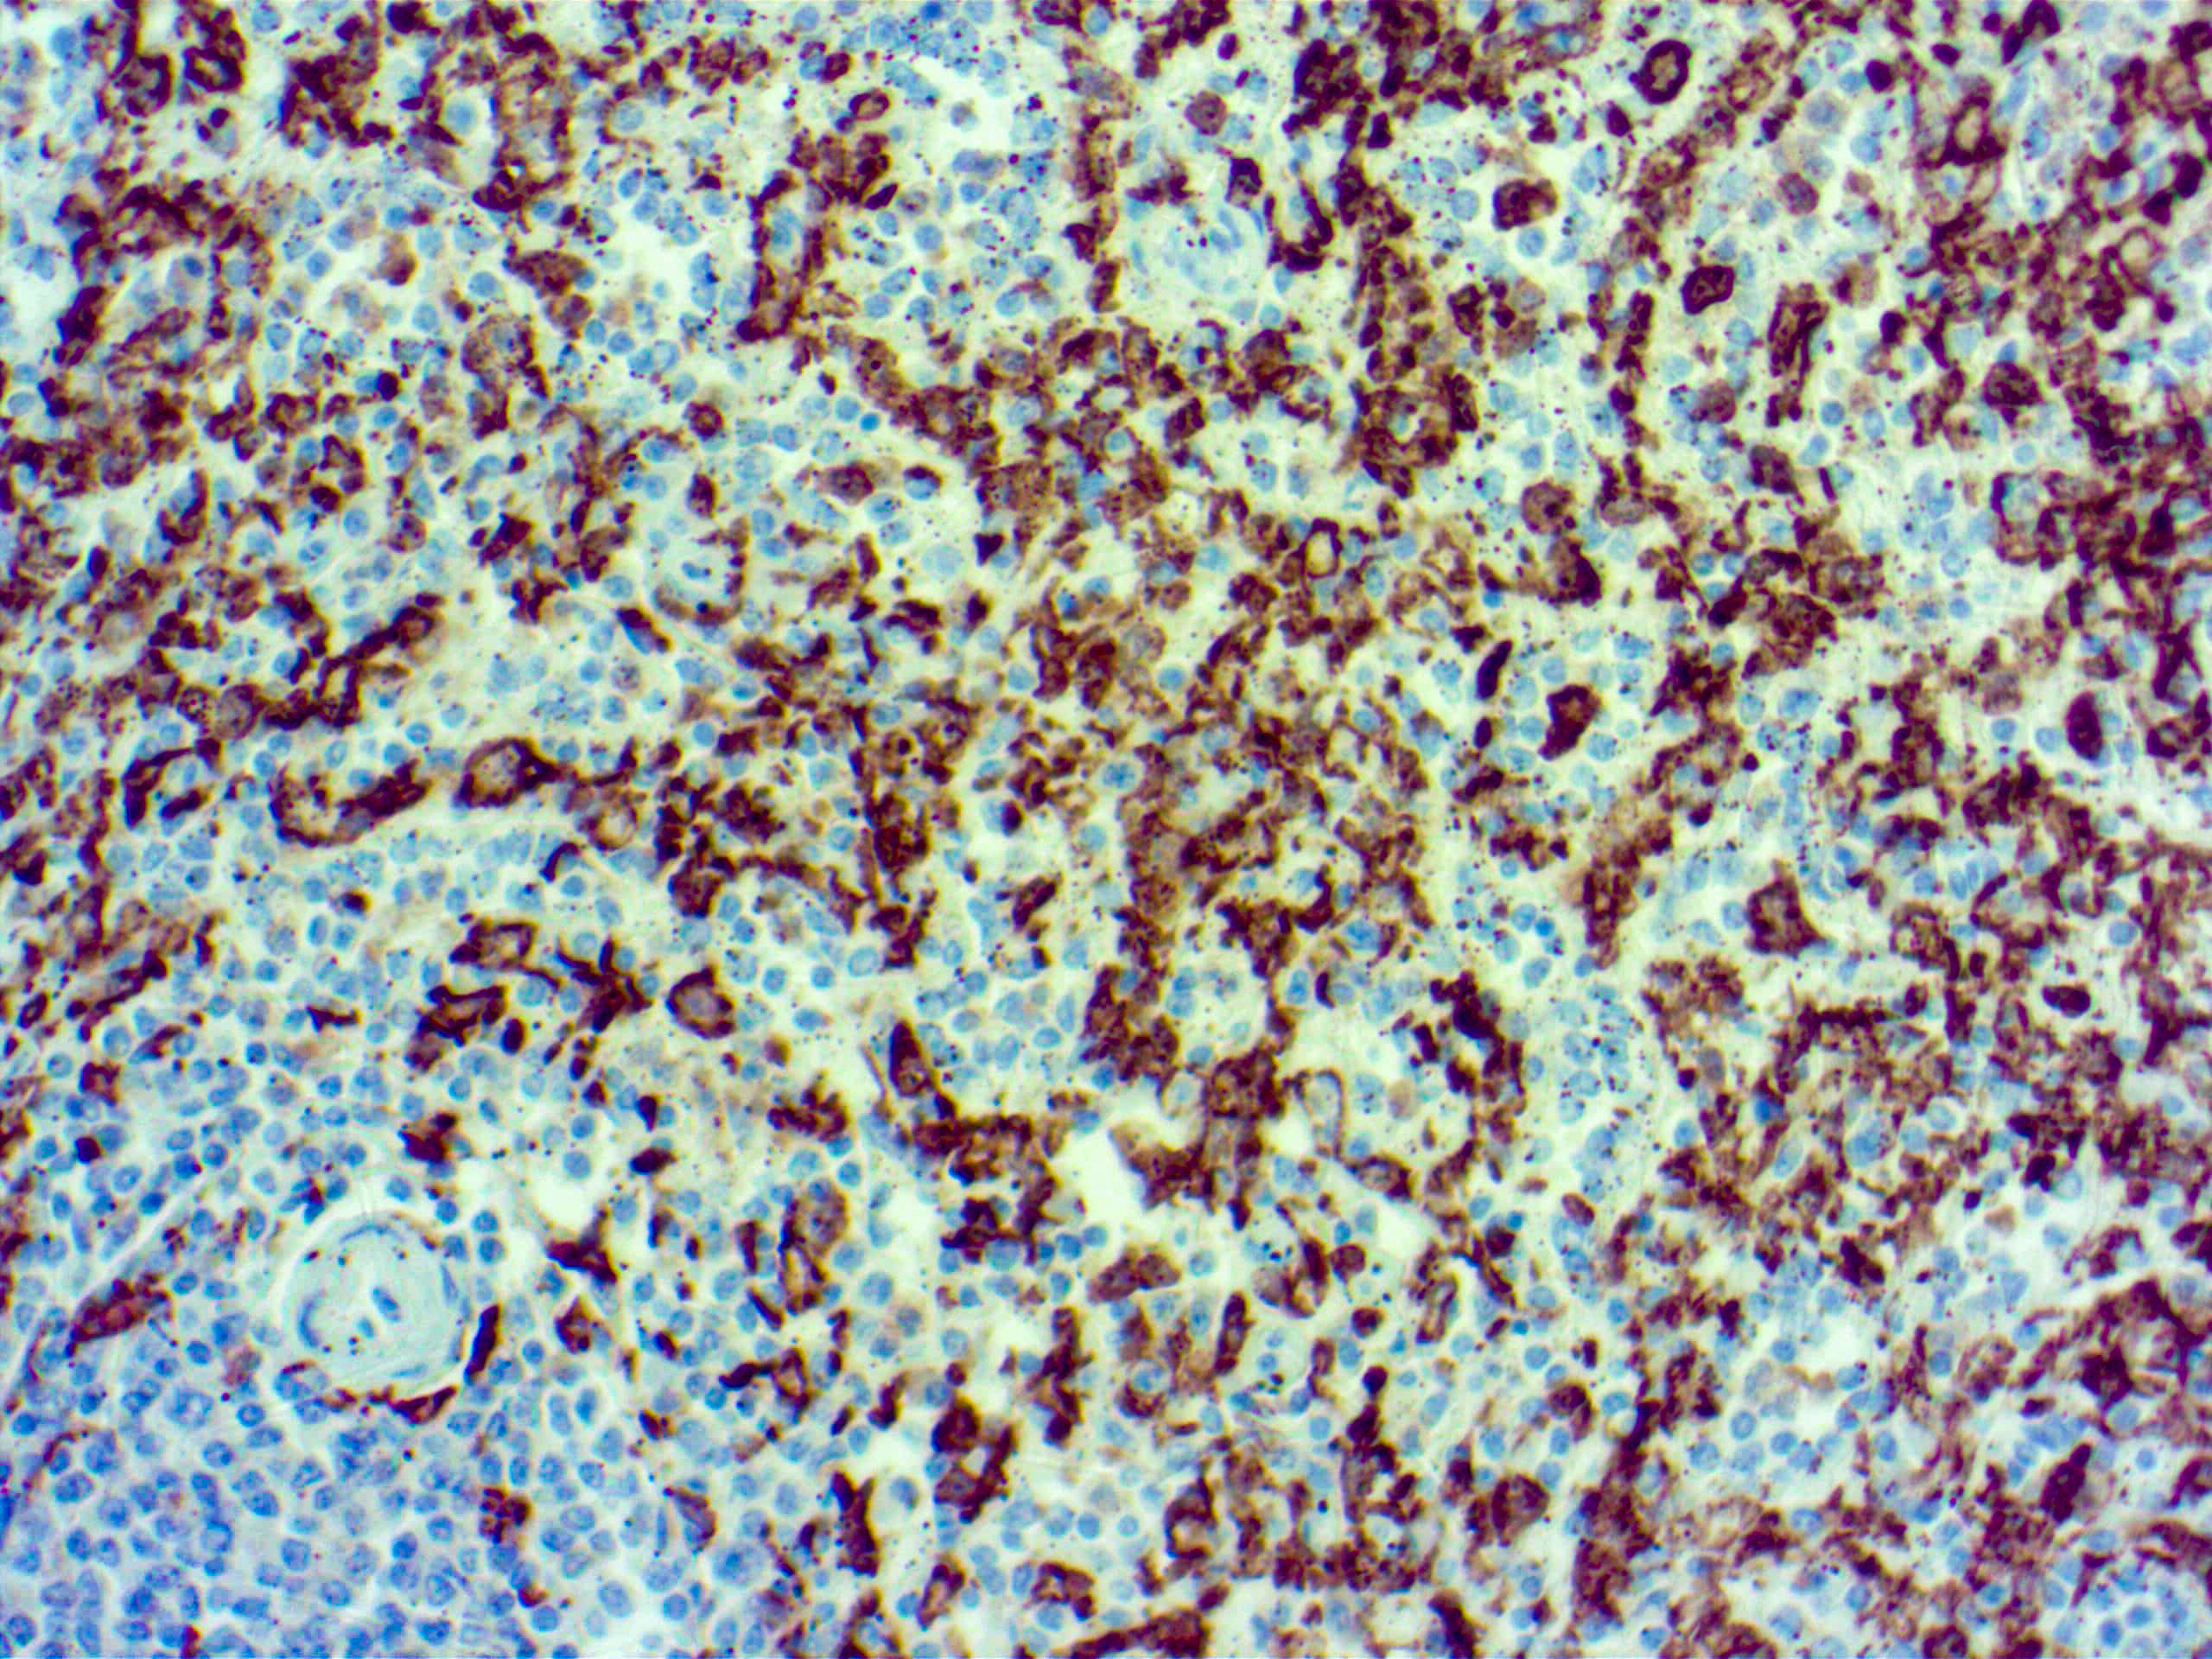

Iba1 (AIF1)

Actin-binding protein that enhances membrane ruffling and RAC activation. Enhances the actin-bundling activity of LCP1. Binds calcium. Plays a role in RAC signaling and in phagocytosis. AIF1 colocalizes with actin, and upon stimulation, translocates to lamellipodia. It is also a marker of human microglia and is expressed by macrophages in injured skeletal muscle. The gene encoding AIF1 resides in the tumor necrosis factor (TNF) cluster of genes, located in the region represented by the human major histocompatibility complex (MHC).

| Positive Control Tissue | Spleen |